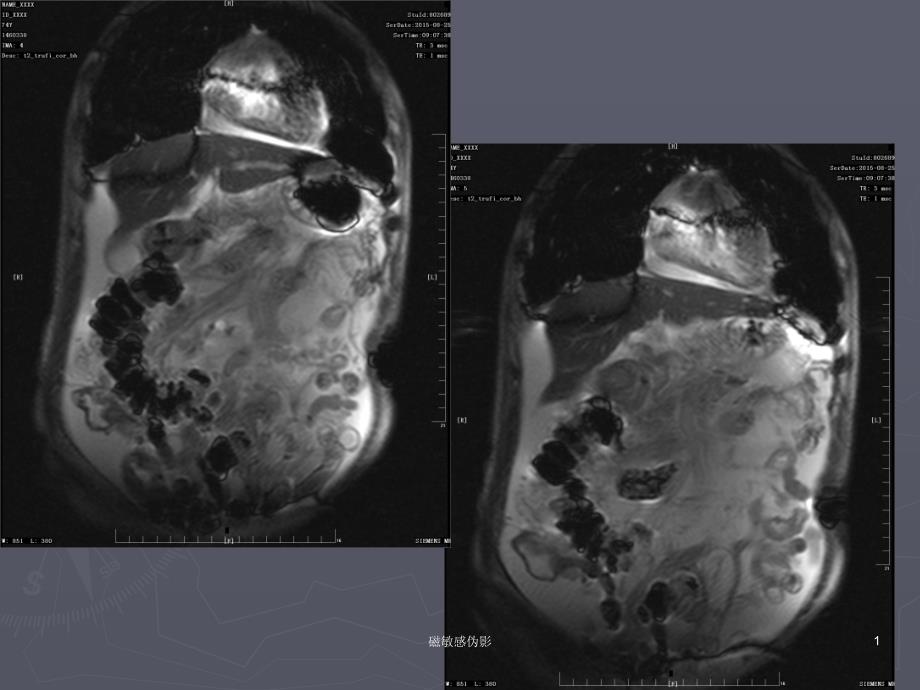

1磁敏感伪影 2磁敏感伪影 3磁敏感伪影 磁敏感伪影 陈海龙陈海龙 2015.09.172015.09.174磁敏感伪影 ►►磁化率是物质的基本特性之一,某种物质的磁化率是指这种物质进入磁场后的磁化强度与外磁场强度的比率►►抗磁性物质磁化率为负值,顺磁性物质的磁化率为正值,一般顺磁性物质的磁化率很低,铁磁性物质磁化率很高►►人体中如骨皮质、肌肉、脂肪、脑组织、肝脏、水基本上是轻度抗磁性的►►空气、组织中的金属离子(如Fe、Mn、Gd)轻度顺磁性的;►►含有铁、钴、镍等固体金属的顺磁性最强,称为铁磁性物质5磁敏感伪影 ►►磁化率伪影(磁敏感伪影)是两种磁化率差别较大的组织界面上,磁场均匀性发生变形,导致氢质子的进动频率改变,加快T2*失相位和信号衰减,在空间上形成MR信号与真实空间位置不匹配,出现的伪影。

表现为局部信号明显减弱或增强,常同时伴有组织变形►►磁敏感伪影分自身磁化率差异伪影和金属附属物伪影6磁敏感伪影 磁敏感伪影具体有以下特点:►►1 1、常出现在磁化率差别较大的组织界面附近,如空、常出现在磁化率差别较大的组织界面附近,如空气与骨间、空气与组织之间等;气与骨间、空气与组织之间等;►►2 2、体内或体外的金属物质特别是铁磁性物质可造成、体内或体外的金属物质特别是铁磁性物质可造成局部磁化率发生显著变化,出现严重的磁敏感伪影;局部磁化率发生显著变化,出现严重的磁敏感伪影;►►3 3、梯度回波序列对磁化率变化敏感,与自旋回波类、梯度回波序列对磁化率变化敏感,与自旋回波类序列相比更容易出现磁敏感伪影,序列相比更容易出现磁敏感伪影,EPIEPI序列的磁敏感序列的磁敏感伪影更为严重;伪影更为严重;►►4 4、、T2WIT2WI或或T2*WIT2*WI的磁敏感伪影较的磁敏感伪影较T1WIT1WI明显7磁敏感伪影 8磁敏感伪影 9磁敏感伪影 10磁敏感伪影 伪影与各参数的关系一、小体素可减少伪影体素是指每个成像单元的大小,体素=(FOV/矩阵)X层厚小体素不能抑制金属本身的磁敏感伪影,但可以提高金属周围变形组织的空间分辨率,减少周围自由水扩散运动造成的信号丢失,减轻伪影干扰小体素可通过增大矩阵、缩小FOV及减小层厚;11磁敏感伪影 256256((0.9x0.9x5.00.9x0.9x5.0)) 448448((0.5x0.5x5.00.5x0.5x5.0))12磁敏感伪影 ►►FOV:400-22013磁敏感伪影 ►►层厚:5mm—3mm14磁敏感伪影 ►►注意:过小FOV易发生卷褶伪影,薄层厚使图像信噪比SNR降低,大矩阵增加了扫描时间。